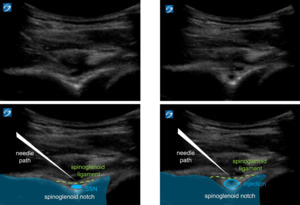

Next, the GHJ is visualized and injected via MSK-US from an in-plane medial to lateral approach. Once needle placement is confirmed, 20-30 cc total injectate is administered (Figure 2). Typically, the injectate includes 40 mg Triamcinolone, if the patient has a hemoglobin A1c < 8.0, and a mixture of 10-19cc of NS or sterile water and 10 cc Ropivacaine. In the poorly controlled diabetic patient with hemoglobin A1c > 8.0, there is the option to substitute steroid with injection of 30mg – 60 mg of Ketorolac, provided that renal function is preserved.